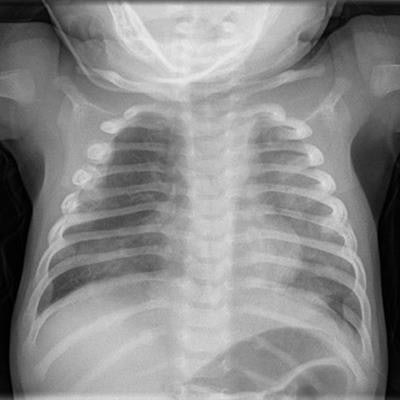

Pediatric imaging requires an in-depth knowledge of the developmental abnormalities and diseases distinct to the pediatric population. In addition, the specialty is vital in cases of actual or suspected physical abuse.

"Failure of radiological provision can have disastrous effects, not only for the child, but also their family and the staff and institutions involved in their care," the authors wrote.